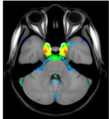

Magnetic resonance angiography (MRA) can capture the variation of cerebral arteries with high spatial resolution. These measurements include valuable information about the morphology, geometry, and density of brain arteries, which may be useful to identify risk factors for cerebrovascular and neurological diseases at an early time point. However, this requires knowledge about the distribution and morphology of vessels in healthy subjects. the statistical arterial brain atlas described in this work is a free and public neuroimaging resource that can be used to identify vascular morphological changes. The atlas was generated based on 544 freely available multi-center MRA and T1-weighted MRI datasets. the arteries were automatically segmented in each MRA dataset and used for vessel radius quantification. The binary segmentation and vessel size information were non-linearly registered to the MNI brain atlas using the T1-weighted MRI datasets to construct atlases of artery occurrence probability, mean artery radius, and artery radius standard deviation. This public neuroimaging resource improves the understanding of the distribution and size of arteries in the healthy human brain.

The statistical atlas consists of four image files in the niftii format and in MNI reference space (0.5 mm^3). These files include the TOF MRA average atlas (tofAverage.nii.gz), the vessel probability atlas (vesselProbabilities.nii.gz [in %]), the mean artery radius atlas (vesselRadius.nii.gz [in mm]), and the standard deviation of the artery radius atlas (vesselRadiusStd.nii.gz [in mm]). All images are saved using float values. The TOF MRA and T1-weighted datasets used for atlas generation can be downloaded from the original sources.